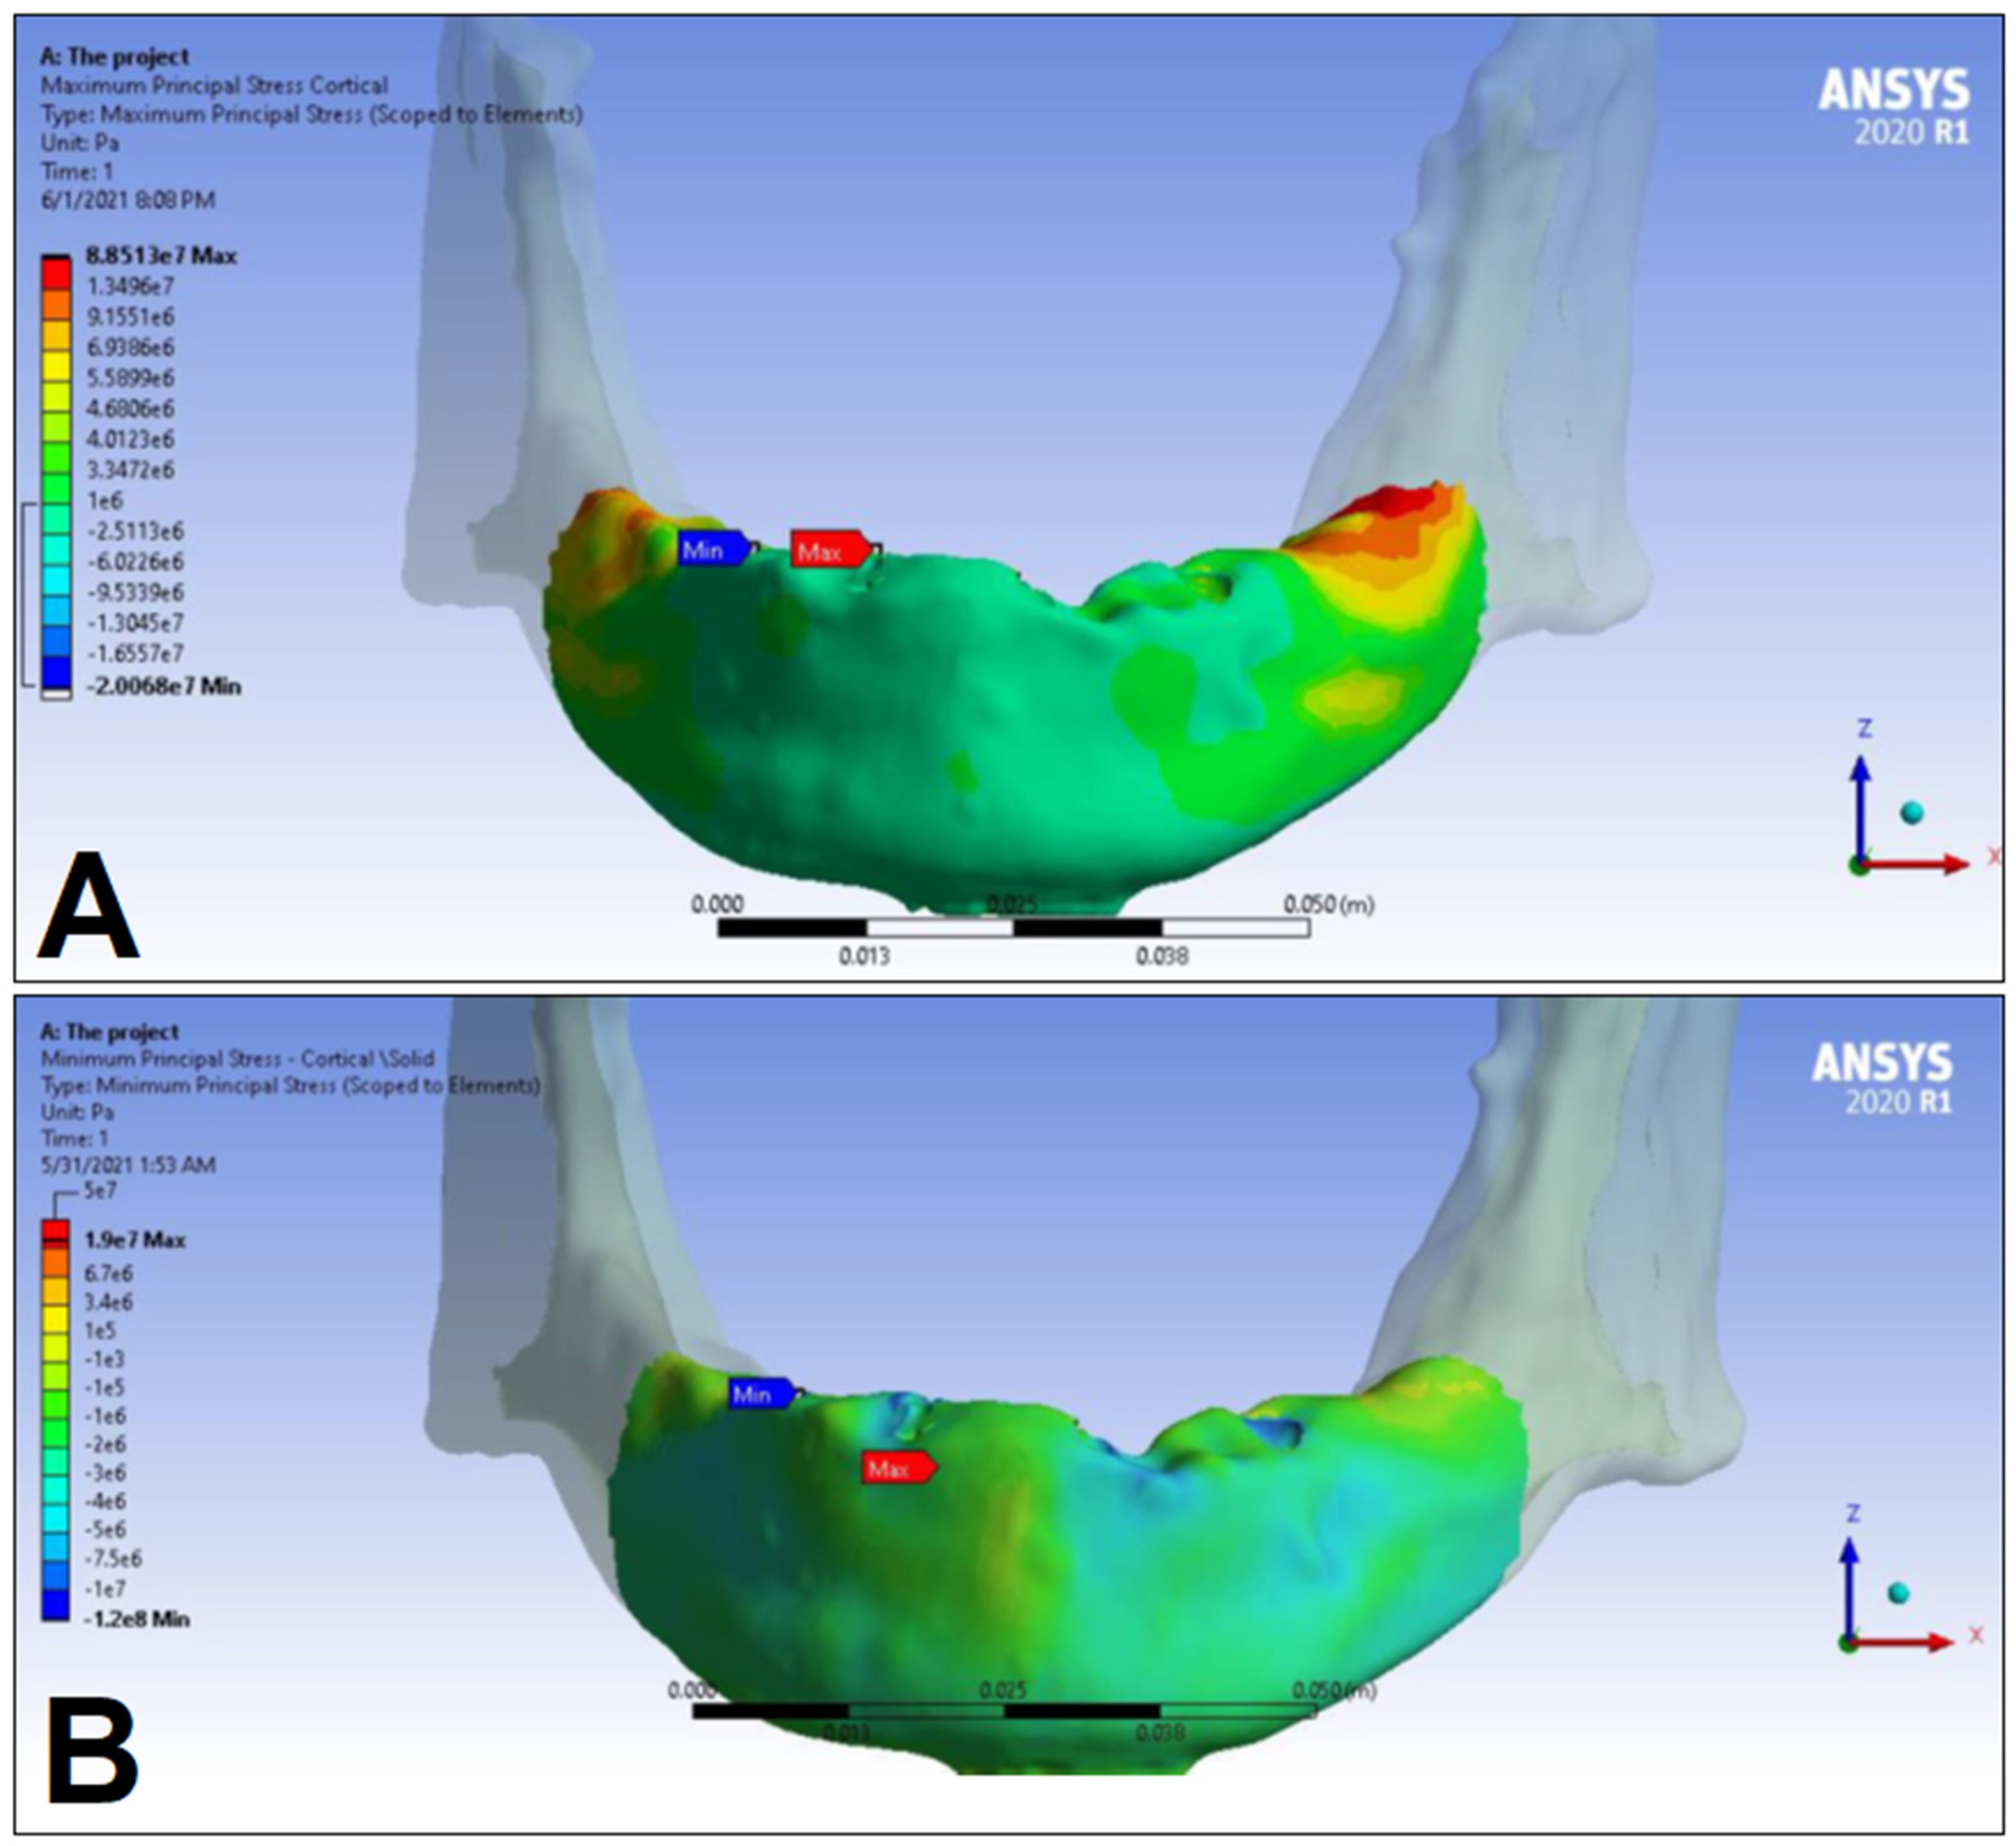

3. Results

| LC1 | LC2 | LC3 | LC4 | ||||||

|---|---|---|---|---|---|---|---|---|---|

| S1 | S2 | S1 | S2 | S1 | S2 | S1 | S2 | ||

| Cortical bone | Pmax [MPa] | 76.39 | 88.51 | 89.57 | 102.98 | 85.63 | 95.48 | 81.02 | 93.15 |

| Pmin [MPa] | −115.30 | −222.76 | −136.4 | −265.35 | −172.30 | −252.61 | −125.20 | −235.32 | |

| Trabecular bone | Pmax [MPa] | 2.49 | 2.24 | 3.03 | 2.62 | 2.95 | 2.52 | 2.92 | 2.59 |

| Pmin [MPa] | −2.81 | −2.89 | −3.34 | −3.38 | −3.25 | −3.25 | −3.49 | −3.52 | |

| Peqv [MPa] | 166.40 | 244.92 | 166.36 | 279.69 | 164.36 | 265.58 | 142.27 | 260.77 | |